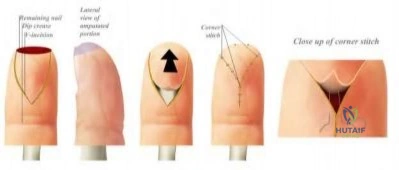

A 9-year-old boy presents to the emergency department after his long finger was crushed in a door. Examination reveals a clinically deformed distal phalanx with the nail plate avulsed proximally, resting dorsal to the eponychial fold. Radiographs show a displaced Salter-Harris I fracture of the distal phalanx. What is the most appropriate management?